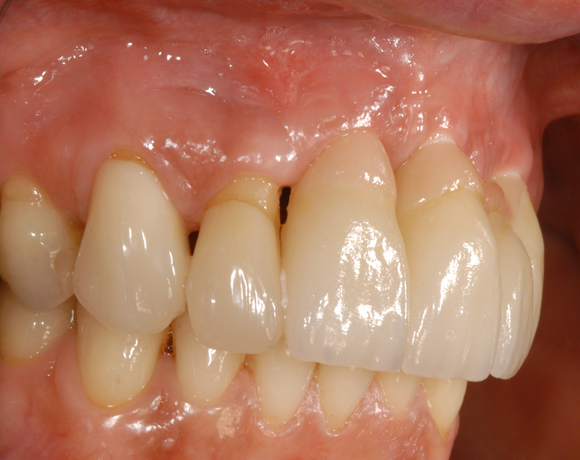

Drei Implantate in der Oberkieferfront

Das vollkeramische zweiteilige Implantat hat durch seine weiße Farbe im Frontzahnbereich keine ästhetischen Nachteile.

Ein Projekt aus dem Jahr 2011

Im vorliegenden Patientenfall mussten die 11 bis 22 aus parodontalen Gründen extrahiert werden. Die Zähne hatten Lockerungsgrad III, und es bestand ein starker horizontaler Knochenabbau. Das Ergebnis zeigt die Abschlusssituation nach Knochenaufbau und der Insertion von drei Vollkeramikimplantaten.